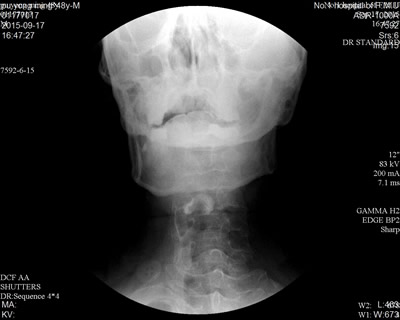

病例:患者,男性,48岁,以“突发右侧肢体无力1月余”为主诉入院。结合影像学表现,诊断为:脑干出血恢复期。患者临床表现为右侧肢体瘫痪伴面瘫。患者在食用稀流质时,常出现呛咳、偶有误吸,曾多次导致肺部感染。经过康复科初期吞咽治疗后,患者呛咳症状较前稍好转。为求进一步精准治疗,康复科专家决定对患者行“吞咽造影录像检查与评估”。在造影下可见:患者在食用对比剂后,单次吞咽,部分食物残留在口腔、会厌谷及梨状窝内(图a、b),经过反复吞咽后可把全部食物送入食管,未见明显呛咳。经过评估,患者的呛咳主要是由于面肌的瘫痪,食物无法有序、可控的输送至咽部所致,经过加强患者面肌收缩动作的训练以及指导患者在进食时进行点头吞咽、交互吞咽,现患者已能够正常进食,无呛咳及误吸的情况发生。

图a 图b